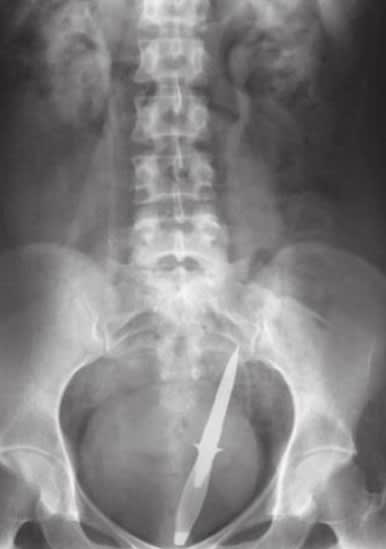

01/09/2017 à 08h09

regardez moi ça 

(Le premier c'est pas un concombre , c'est une courgette, le 3eme c'est une lampe torche)

Quelqu'un a t il perdu ses clés ?